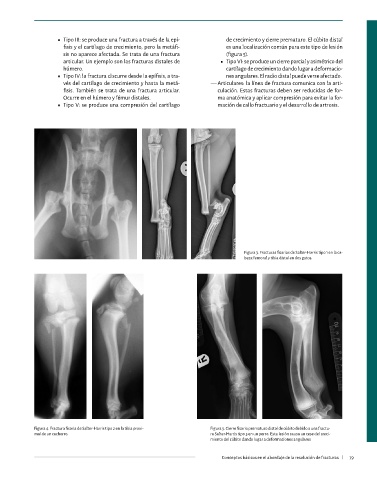

Figura 3. Fracturas fisarias de Salter-Harris tipo 1 en la ca-

beza femoral y tibia distal en dos gatos.

Figura 1. Fractura diafisaria media de húmero en un gato.

Figura 2. Fractura metafisaria conminuta de húmero en Figura 4. Fractura fisaria de Salter-Harris tipo 2 en la tibia proxi- Figura 5. Cierre fisario prematuro distal de cúbito debido a una fractu-

un gato. mal de un cachorro. ra Salter-Harris tipo 5 en un perro. Esta lesión causa un cese del creci-

miento del cúbito dando lugar a deformaciones angulares